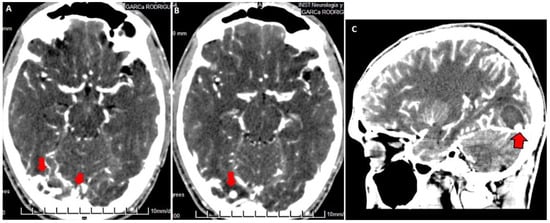

3.2. Imaging Studies